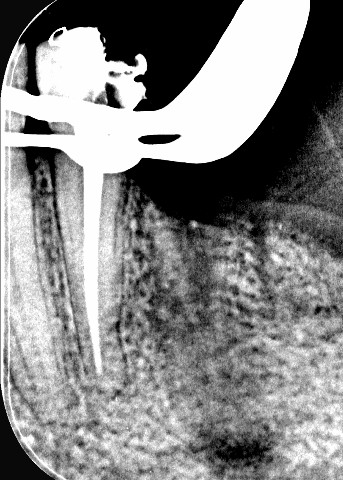

Complex endodontic case